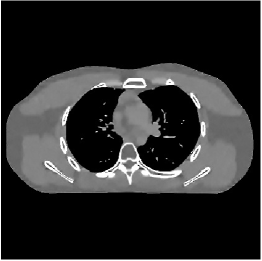

III-B2 Algorithm Convergence Rate

Our main concern in convergence rates of Algorithm 1 lies with an inaccurate preconditioner (e.g., circulant one) particularly for the 3D sparse-view CT reconstructions. To see the effects of using a loose preconditioner in Algorithm 1, we compared the convergence rates of the 3D case with those of 2D (Fig. 5(a) and Fig. 5(b)). In the first iterations, Algorithm 1 converges faster in 2D experiments than 3D experiments. However, after iterations, the convergence rates of Algorithm 1 are similar in both 2D and 3D reconstructions. In addition, more PCG (with a circulant preconditioner) iterations does not significantly accelerate Algorithm 1 (see Fig 2). These empirically observations imply that, in the 3D sparse-view CT reconstructions, Algorithm 1 using a circulant preconditioner ( PCG iterations) is a reasonable choice.

| views | ||||

|---|---|---|---|---|

| (a) , | (b) , | (c) , | (d) , |